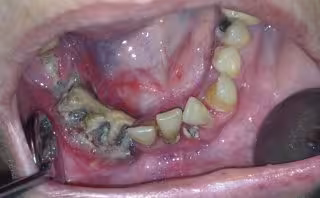

Imagen de paciente afectada de osteonecrosis mandibular por bifosfonatos

Además, prosigue, en el empleo de los fármacos que se utilizan para el tratamiento de esta enfermedad, los bifosfonatos, ampliamente difundidos entre la población, donde ha aparecido un nuevo proceso patológico, la osteonecrosis maxilar o mandibular.